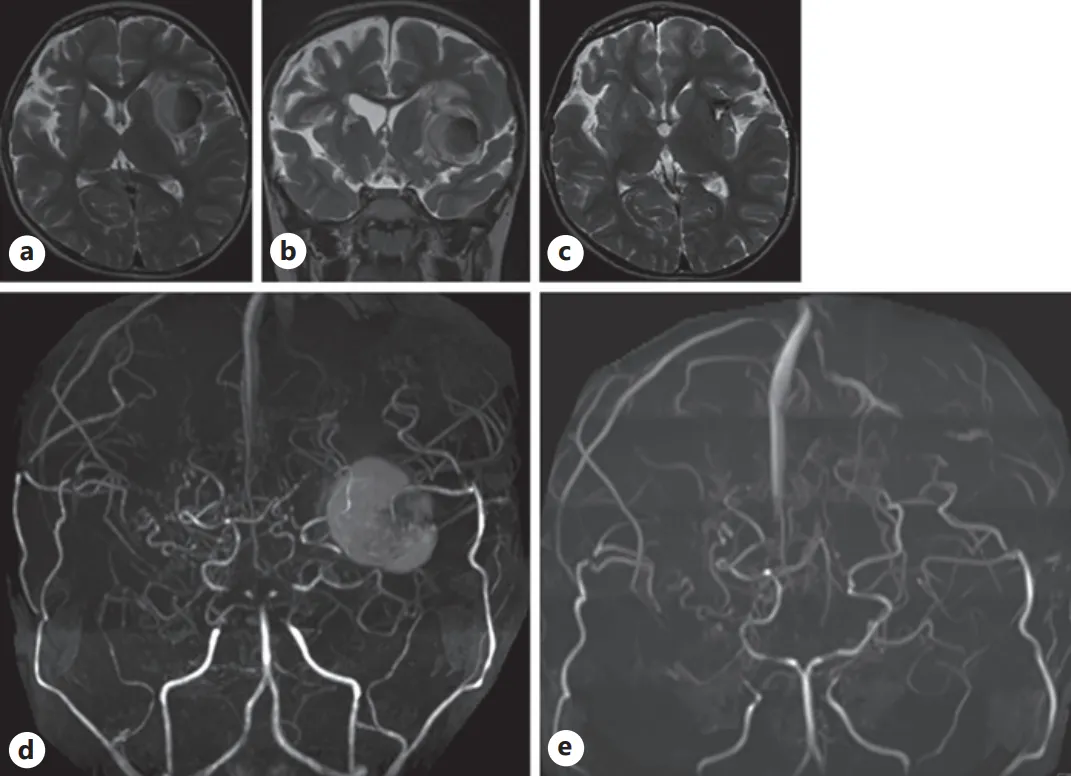

随访轴位(a)与冠状位(b)T2加权磁共振成像(MRI)图像。可见左侧岛叶病灶扩大至两倍以上,周围伴有水肿组织。

(c)术后T2加权MRI显示,原异常病灶已被手术疤痕组织取代。术前(d)与术后(e)磁共振血管造影(MRA)。术前MRA上的较大病灶在术后影像中已消失。